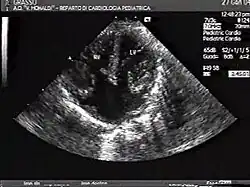

Atrioventricular canal defect is a combination of abnormalities of the heart and is present at birth. There is a problem when there are holes present in the walls that separate chambers (septa), as well as when valves are incorrectly constructed. There are other names for these heart abnormalities such as endocardial cushion defects or atrioventricular septal defect.[4]

Atrioventricular canal defect may be divided into partial or complete forms. In the partial form, openings between the left and right atria and improper formation of the mitral valve exist. In the complete form, there is free movement in all chambers because there is a large hole where the atria and ventricles meet, and instead of there being two valves there is one common valve.[4]